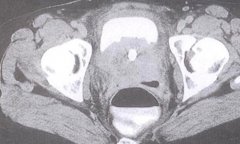

母婴血型不合:母婴血型不合的溶血病以RH和ABO这两个系统血型不合最为常见,其中,RH溶血病常发生在母亲为RH阴性而父亲为RH阳性的例子中。RH阴性的人数只占人口的0.3%,发生RH阴阳不合的机率并不高。

母儿血型不合,常见的有ABO血型不合和Rh血型不合两大类型。ABO血型不合比较常见,一般孕妇为O型,丈夫为A型、B型或AB型,可以发生胎儿或新生儿溶血症。